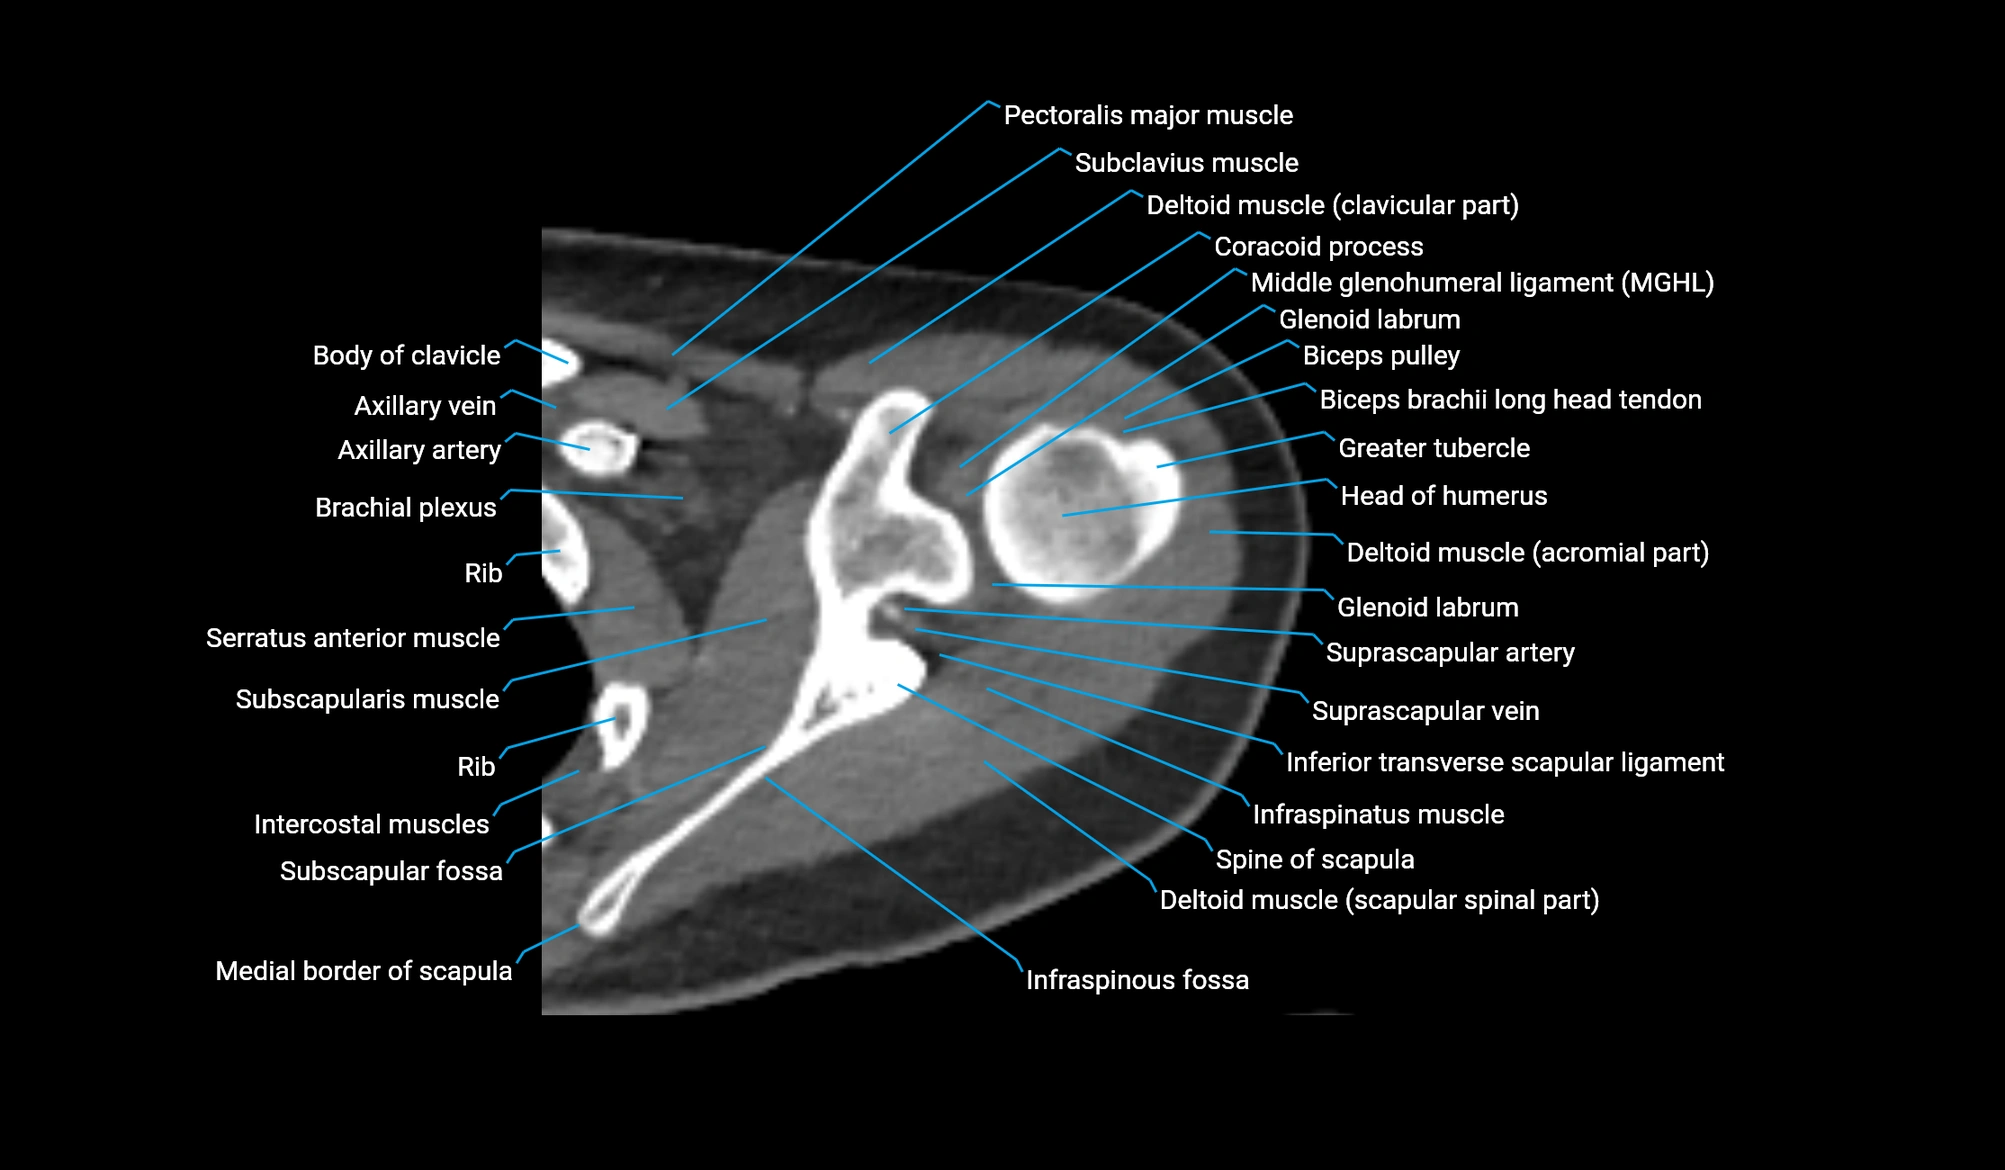

- Biceps pulley

- Brachial plexus

- Clavicular part of deltoid muscle

- Coracoid process of scapula

- Glenoid labrum

- Head of humerus

- Inferior transverse scapular ligament

- Infraspinatus muscle

- Infraspinous fossa

- Middle glenohumeral ligament

- Pectoralis major muscle

- Scapular spinal part of deltoid muscle

- Spine of scapula

- Subclavius muscle

- Subscapular fossa

- Subscapularis muscle